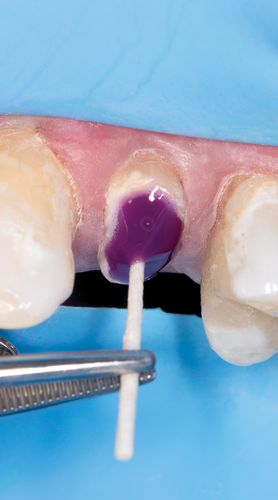

Fig 14. Application of universal adhesive onto the walls and base of the channel.

Figure 14